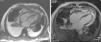

Dois meses após início da terapêutica tuberculostática, a reavaliação ecocardiográfica revelou sinais de constrição pericárdica (septal bounce, variação respiratória significativa do fluxo transvalvular cardíaco e do fluxo venoso hepático – Figura 3) associados a pequena lâmina de derrame pericárdico. Foi solicitada RMN cardíaca, que confirmou estes achados e revelou espessamento do pericárdio, sem aumento da intensidade de sinal após injeção de contraste e com extensa área de realce tardio, bem como zonas de continuidade com o miocárdio e sinais de fisiologia constritiva (septal bounce) (Figura 4). Clinicamente, e durante o terceiro mês de terapêutica dirigida, observou‐se o desenvolvimento de um quadro de insuficiência cardíaca de predomínio direito que motivou novo internamento e que foi rapidamente progressivo, evoluindo para anasarca, disfunção hepática, enteropatia exsudativa e caquexia. Atendendo ao diagnóstico de pericardite efusiva‐constritiva, com deterioração clínica rapidamente progressiva e sinais de cronicidade, foi referenciado para terapêutica cirúrgica e submetido a pericardiectomia. No intraoperatório observou‐se uma sínfise pericárdica completa, com aspeto macroscópico sugestivo de infiltração tumoral (Figura 5). Foi efetuada uma descorticação parcial, atendendo à dificuldade técnica condicionada pela presença de zonas de continuidade entre o pericárdio e o miocárdio.

Depois da ecocardiografia, a RM cardíaca é o método de imagem de escolha para o estudo do pericárdio. Devido à sua composição fibrosa, o pericárdio saudável revela‐se como uma estrutura hipointensa nas sequências ponderadas em T1 e T2. Na pericardite constritiva, as características morfológicas típicas são o espessamento global das lâminas do pericárdio (>4mm em espessura) e a presença de realce tardio no pericárdio, que se correlaciona com a fase aguda da inflamação pericárdica8. A RM permite ainda a adequada diferenciação entre derrames pericárdicos de pequenas dimensões e o espessamento pericárdico, a deteção do septal bounce e da aderência entre o pericárdio e o miocárdio2. A TC cardíaca também é útil no diagnóstico da pericardite constritiva, na medida em que permite demonstrar o espessamento e a calcificação pericárdicos, tal como a dilatação da VCI e a angulação do SIV. A perda do comportamento pulsátil das estruturas pulmonares imediatamente adjacentes ao coração, associada ao espessamento pericárdico, é altamente sugestiva de uma fisiologia constritiva3. Destaca‐se o valor adicional destes dois métodos de diagnóstico, sobretudo quando as variações respiratórias ecocardiográficas são equívocas, bem como quando nos encontramos na presença de outras condições clínicas que podem estar associadas ao aumento da variação respiratória dos fluxos transvalvulares, como sejam a obesidade e a doença pulmonar obstrutiva crónica9.